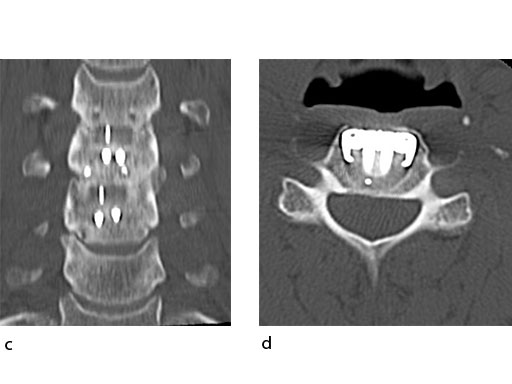

A 51-year-old woman was affected by cervical radiculo-myelopathy due to spinal and neuroforaminal stenosis. The preoperative CT scans are shown at Fig 4 and MRI at Fig 5.

The patient was treated by anterior cervical decompression and fusion (ACDF) with ZERO-P filled with ChronOS. No autologous bone graft was used. Postoperative images are shown (Fig 69).